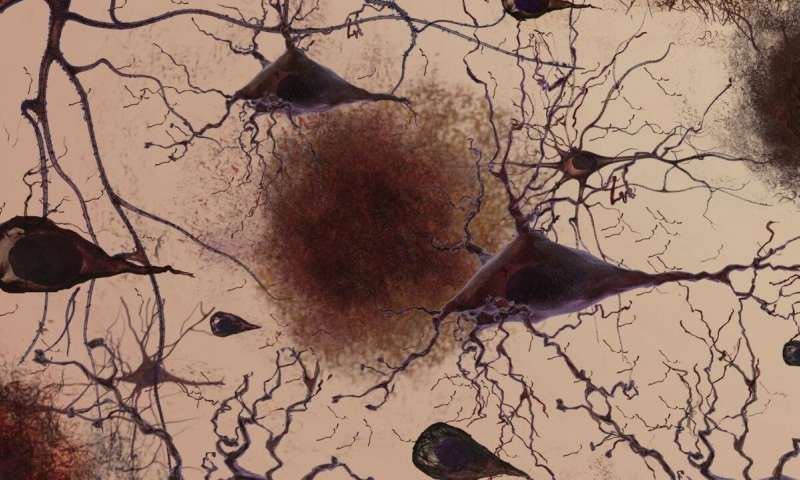

AD的发病机制尚不清楚,但在显著的症状出现之前,患者大脑中就产生了β-淀粉样蛋白斑块的沉积等病理学变化。

阿尔兹海默病(AD)是一种起病隐匿的进行性神经退行性疾病,表现为记忆力减退和认知功能障碍。AD的发病机制尚不清楚,但在显著的症状出现之前,患者大脑中就产生了β-淀粉样蛋白斑块的沉积等病理学变化。这种病理标志物的检测往往涉及侵入性损伤和昂贵的试剂;用影像学检测到异常蛋白沉积时已经太迟,此时大脑的结构和功能已经发生了不可逆的损伤。因此寻找非侵入性的AD预测手段迫在眉睫。

研究者发现Obj-SCD组起始数据和认知正常组几乎没有差距,但是在4年中,其脑中淀粉样蛋白沉积的累积增长速率更快,并且其内嗅皮层也发生明显萎缩。内嗅皮层与海马联系紧密,与记忆、定位和时间观念密切相关,也是在AD早期首当其冲的脑区。这说明Obj-SCD者虽然没有表现出明显的AD的症状和器质改变,但已经处于罹患此病的风口浪尖。

轻微认知障碍组初始的淀粉样蛋白累积量更高、内嗅皮层和海马萎缩更严重,并且随实验进展海马体积减小速度较Obj-SCD和认知正常组更快,说明此时AD已经波及大脑众多部位。然而,MCI组淀粉样蛋白累积的速度却不及Obj-SCD组,说明精细认知困难阶段是AD发展的关键时期。

阿尔兹海默病的源起是多因素共同作用的结果,例如基因、生活习惯和环境因素等,最重要的即为衰老。在此过程中,累积的淀粉样蛋白斑块会逐渐杀死神经元,造成认知功能的损害以及生活能力的丧失。尽管有一系列针对AD的药物,包括刚刚上市的“九期一”,但是对于这种无解的疾病,早发现早治疗是最好的临床策略。